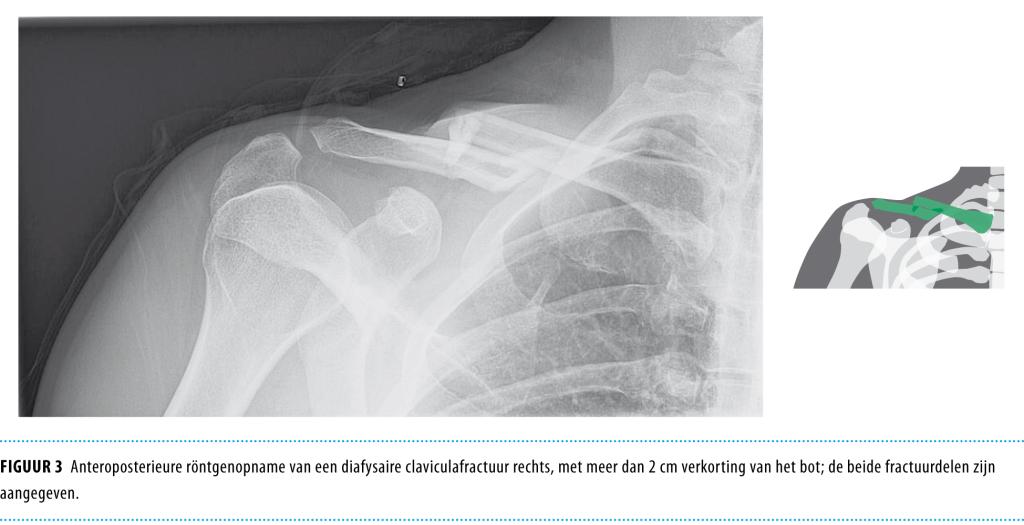

• Traditioneel werden diafysaire claviculafracturen conservatief behandeld. Voor bepaalde fracturen blijkt een operatieve behandeling echter voordelen te hebben. Dit blijkt uit een literatuuroverzicht.

• De ongedislokeerde midclaviculaire fractuur kan uitstekend conservatief worden behandeld, bij voorkeur met een ‘sling’.

• Gedislokeerde fracturen leiden vaker tot ‘nonunion’ en ‘malunion’. Intramedullaire fixatie kan worden overwogen bij simpele gedislokeerde fracturen, maar zal in geval van comminutieve fracturen lengte en rotatie niet optimaal kunnen behouden. Plaatosteosynthese is voor alle claviculafracturen bruikbaar, en levert een reductie van het relatieve risico op nonunion van 86% op.

• Men moet osteosynthese overwegen bij patiënten met een gedislokeerde of comminutieve midclaviculaire fractuur, gezien de toegenomen kans op non- en malunion en op een slechtere functionele uitkomst. Daarbij moet men rekening houden met verwachtingen en leefstijl van de patiënt.